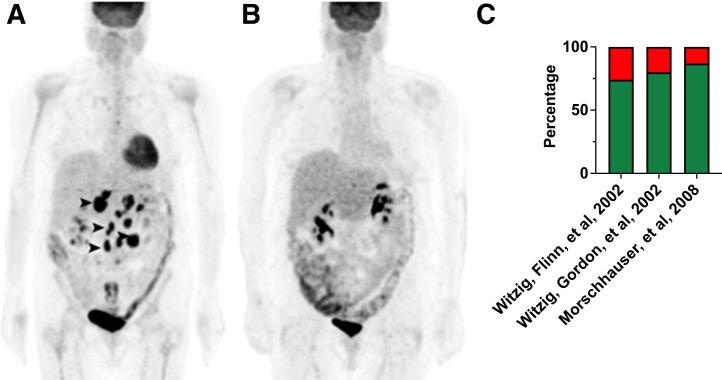

In the early 2000s, major clinical trials provided evidence of a favorable outcome from antibody-mediated radioimmunotherapy for hematologic neoplasms, which then led to Food and Drug Administration approval. For instance, the theranostic armamentarium for the referring hematooncologist now includes Y-ibritumomab tiuxetan for refractory low-grade follicular lymphoma or transformed B-cell non-Hodgkin lymphoma, as well as I-tositumomab for rituximab-refractory follicular lymphoma. Moreover, the first interim results of the SIERRA phase III trial reported beneficial effects from the use of I-anti-CD45 antibodies (Iomab-B) in refractory or relapsed acute myeloid leukemia. During the last decade, the concept of theranostics in hematooncology has been further expanded by C-X-C motif chemokine receptor 4-directed molecular imaging. Beyond improved detection rates of putative sites of disease, C-X-C motif chemokine receptor 4-directed PET/CT also selects candidates for radioligand therapy using β-emitting radioisotopes targeting the identical chemokine receptor on the lymphoma cell surface. Such image-piloted therapeutic strategies provided robust antilymphoma efficacy, along with desired eradication of the bone marrow niche, such as in patients with T- or B-cell lymphoma. As an integral part of the treatment plan, such radioligand therapy-mediated myeloablation also allows one to line up patients for stem cell transplantation, which leads to successful engraftment during the further treatment course. In this continuing education article, we provide an overview of the current advent of theranostics in hematooncology and highlight emerging clinical applications.

在 21 世纪初,几项大型临床试验为血液系统恶性肿瘤的抗体介导的放射免疫治疗提供了有利结果的证据,随后获得了食品和药物管理局的批准。例如,现在,血液肿瘤学家的治疗武器库包括用于难治性低级别滤泡淋巴瘤或转化 B 细胞非霍奇金淋巴瘤的 Y-碘替比单抗替曲膦,以及用于利妥昔单抗难治性滤泡性淋巴瘤的 I-替西莫单抗。此外,SIERRA 三期试验的首次中期结果报告了使用 I-抗-CD45 抗体(Iomab-B)治疗难治性或复发性急性髓系白血病的有益效果。在过去十年中,血液肿瘤学中的治疗学概念通过 C-X-C 基序趋化因子受体 4 定向分子成像得到了进一步扩展。除了提高潜在疾病部位的检测率外,C-X-C 基序趋化因子受体 4 定向 PET/CT 还选择了使用针对淋巴瘤细胞膜上相同趋化因子受体的 β 发射放射性同位素进行放射性配体治疗的候选者。这种基于图像的治疗策略提供了强大的抗淋巴瘤疗效,并期望消除骨髓龛,例如在 T 或 B 细胞淋巴瘤患者中。作为治疗计划的一个组成部分,这种放射性配体治疗介导的骨髓清除也允许患者进行干细胞移植,这导致在进一步的治疗过程中成功植入。在这篇继续教育文章中,我们概述了血液肿瘤学中治疗学的当前发展,并强调了新的临床应用。